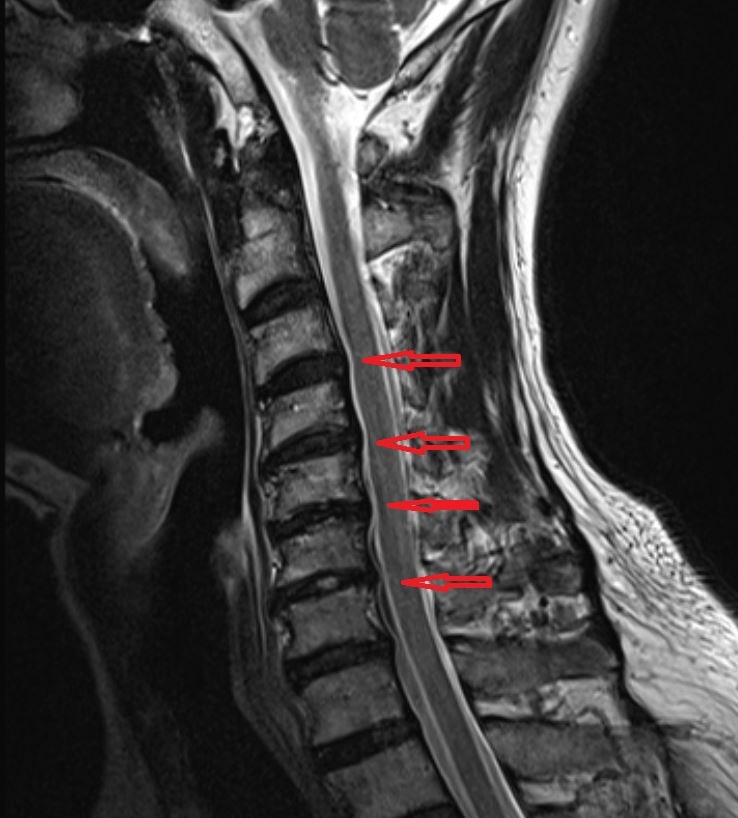

MRI 영상에서는 돌출된 디스크가 신경을 누르는 모습을 확인할 수 있습니다.

압박되는 신경 위치에 따라 저림이 나타나는 손가락 부위도 달라집니다.

경추 C5–6 신경 압박 : 엄지손가락 부위

경추 C6–7 신경 압박 : 검지와 중지

경추 C7–흉추 T1 신경 압박 : 네 번째, 다섯 번째 손가락

이와 같은 분포를 통해 어느 신경이 영향을 받는지 추정할 수 있습니다.